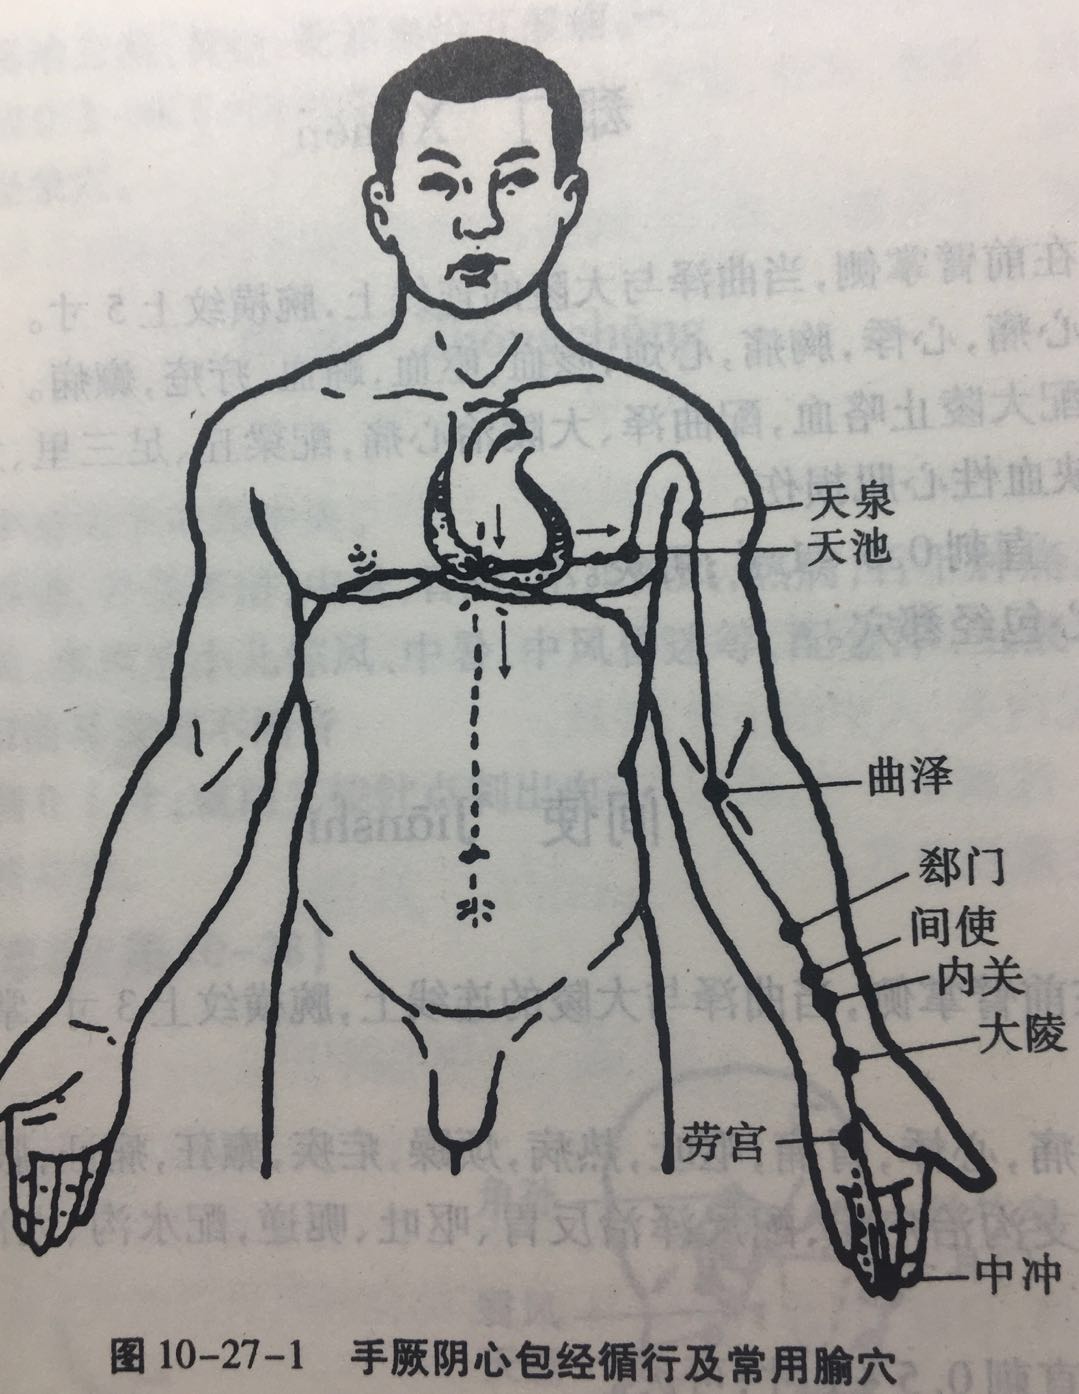

【(九)手厥阴心包经(图 10-27-1)】

2、歌诀 九穴心包手厥阴,天池天泉曲泽深,郄(xì)门间使内关对,大陵劳宫中冲侵。

3、经脉循行 起于胸中,出属心包络,向下通膈,从胸至腹依次联络上、中、下三焦。

胸部支脉:沿胸中,出于胁肋至腋下(天池),上行至腋窝中,沿上臂内侧行于手太阴和手少阴经之间,经肘窝下行于前臂中间进入掌中,沿中指到指端(中冲)。

掌中支脉:从劳宫分出,沿无名指到指端(关冲),与手少阳三焦经相接。

4、主要病候 心痛、胸闷、心惊、心烦、癫狂、腋肿、肘臂挛痛、掌心发热等。

5、主治概要 主治心、胸、胃、神志病及经脉循行部位的其他病证。